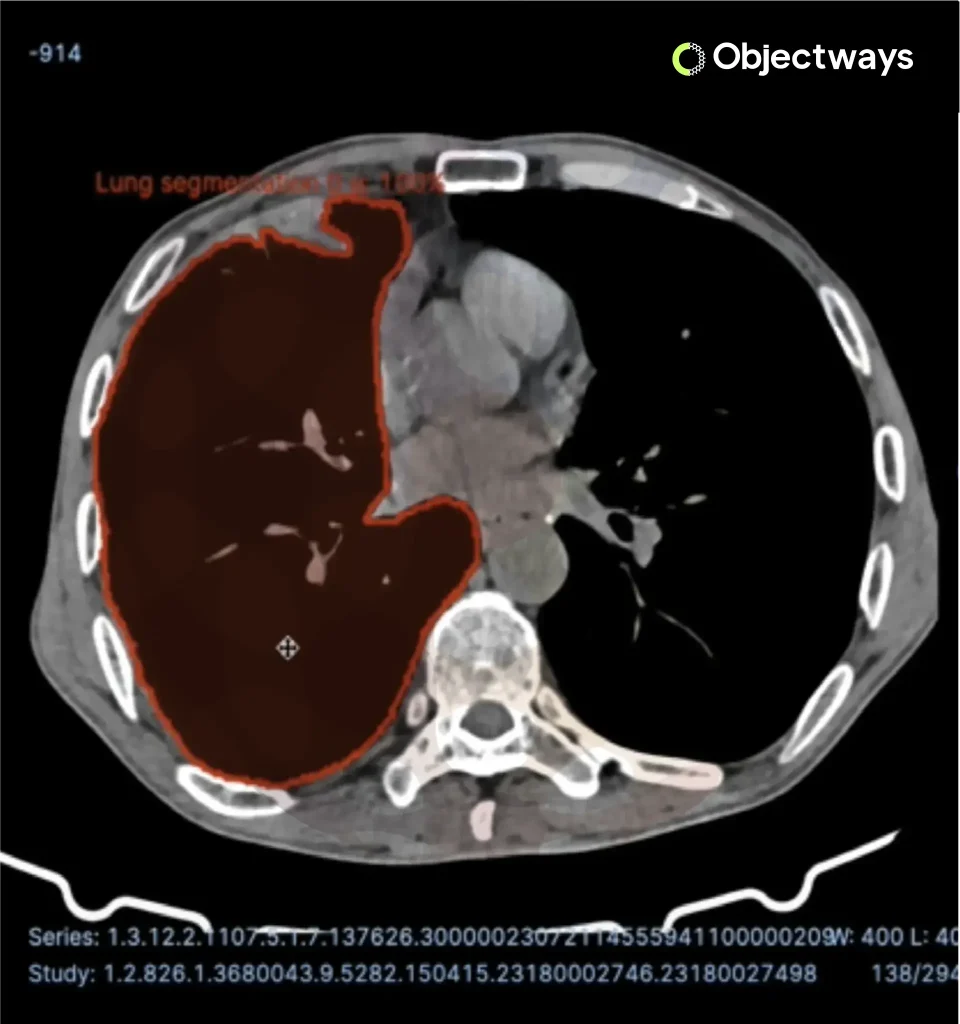

Deep learning is changing medical imaging by making diagnoses faster and more accurate. Radiologists once relied solely on manual scans of X-rays, MRIs, or CT scans, a process that could be slow and prone to error.

Today, computer vision using convolutional neural networks can analyze these images at scale, identifying patterns associated with conditions such as tumors. This provides doctors with stronger support, enabling them to detect diseases earlier and enhance patient care.

Brain Tumor Detection Based on Deep Learning (Source)